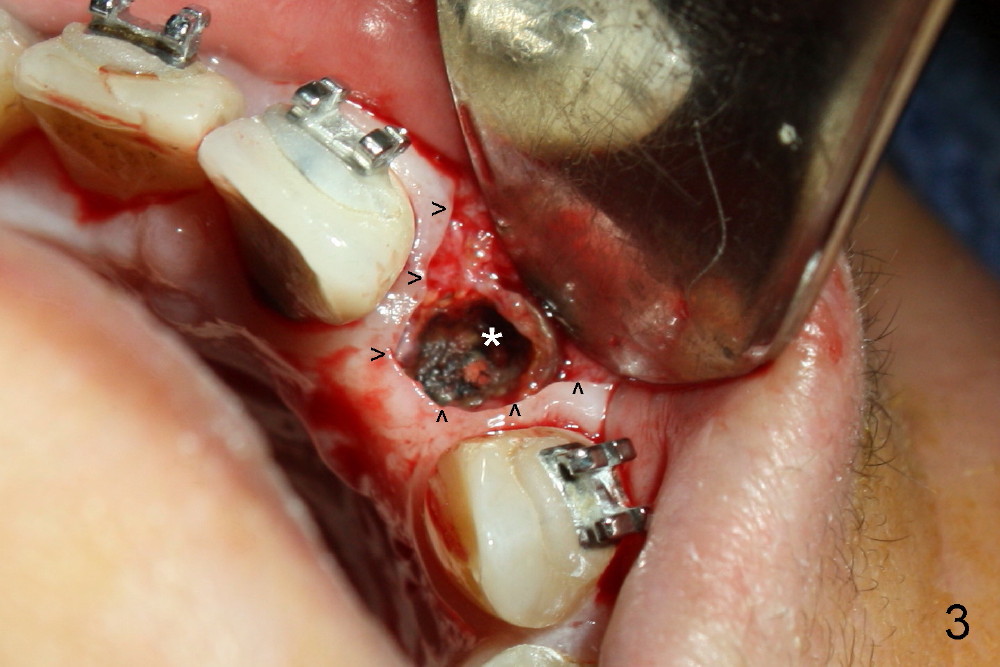

A 56-year-old Oriental lady is going to have immediate implant for the upper left lateral incisor after lengthened preparation (1 2 3 4). There is an indistinct fistula (Fig.1 <) and purulent discharge on anesthetic injection (Fig.2 <). The residual root is exposed (Fig.3 *) following a trapezoidal incision (arrowheads). After tooth extraction and socket debridement with a serrated curette (Fig.4), copious irrigation is conducted with a large monojet and normal saline (Fig.5). The socket will be soaked with non-woven gauze saturated with Clindamycin (Fig.6). The advantage of this antibiotic over Amoxicillin is that there is less mess with the former (completely dissolves). But Clindamycin is bitter. This amalgam well is saved to keep autogenous bone from the reamer and mix with allograft if needed.